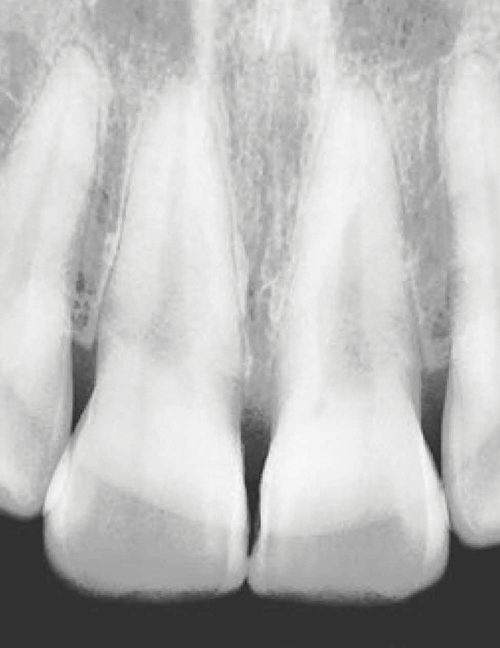

IMAGEM NÍTIDA

Tão nítida quanto o raio-X padrão.

Clareza aprimorada pelo FOCAL SPOT.

70kV, 2mA

*a imagem acima está sujeita a alterações com base no sensor.